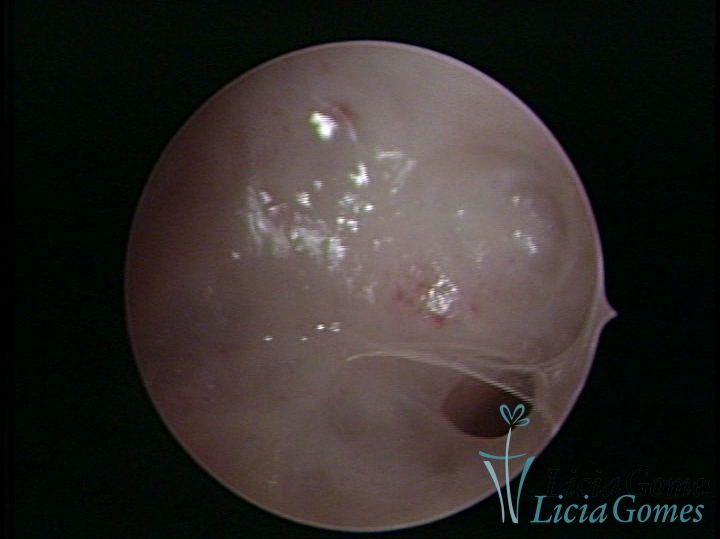

• SINÉQUIA TIPO FIBROSA